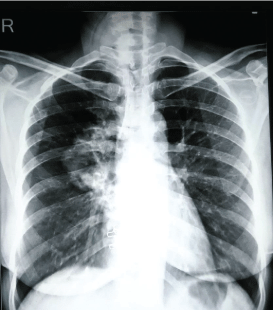

Figure 1: Chest x-ray showed ill-defined rounded heterogeneous opacity.